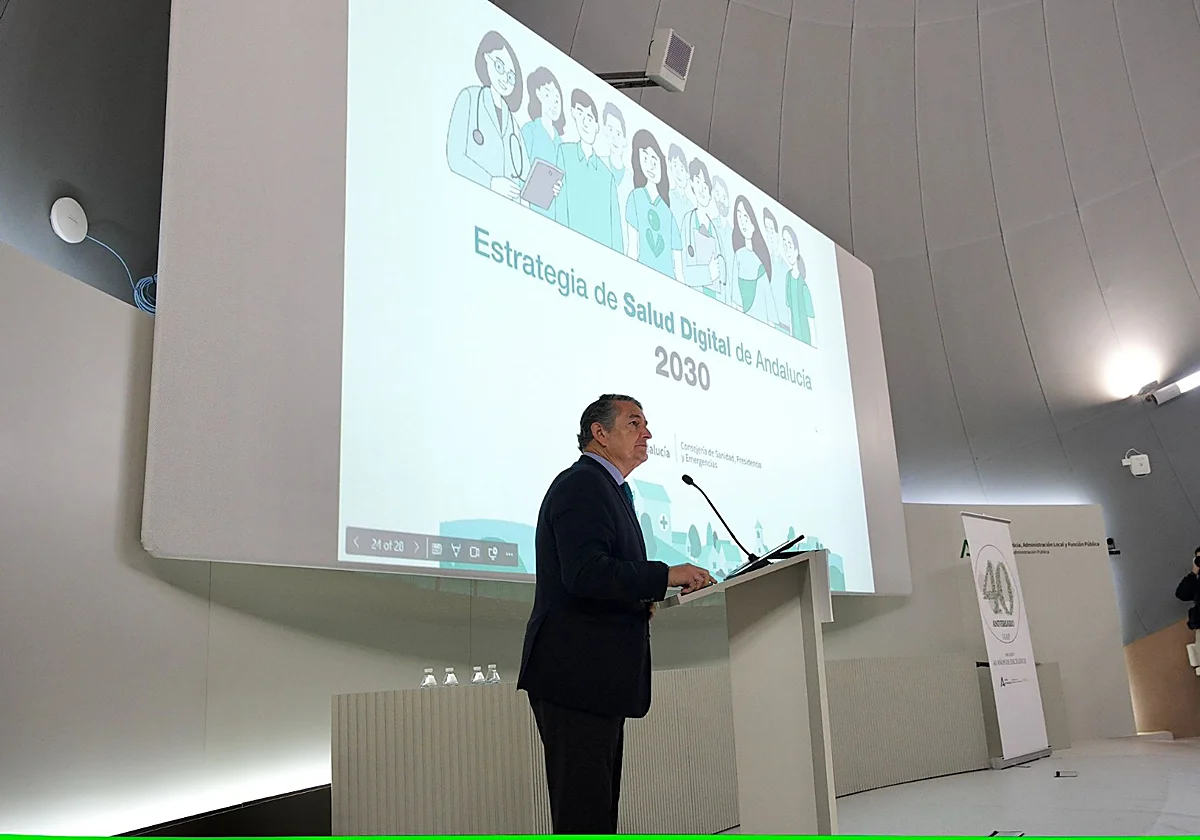

The regional government is merging all healthcare apps into a single 'Salud Responde+' platform to streamline appointments and medical records via mob...